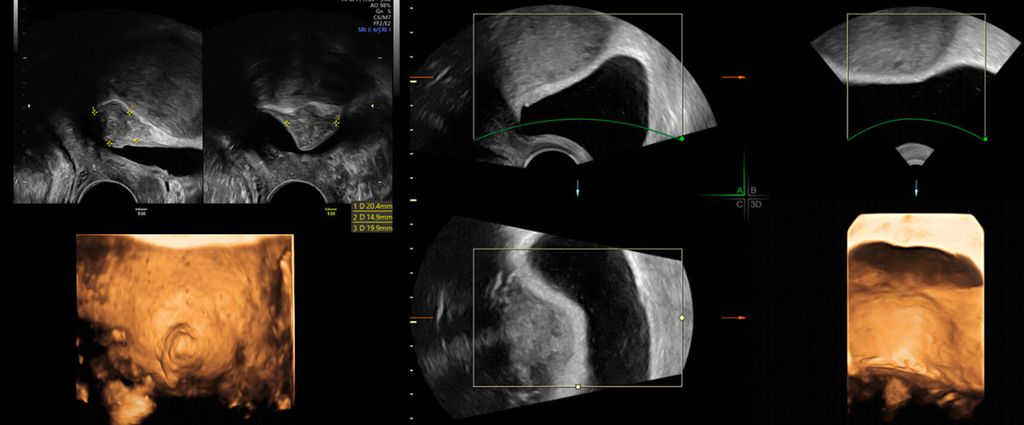

Die Untersuchung wird idealerweise bei hoch aufgebautem Endometrium durchgeführt. Nach Erstellung der Koronarebene kann sowohl die äussere als auch die innere Uteruskontur dargestellt und die Fundusdicke («fundal thickness», FTH) bestimmt werden (Abb. 2). Eine allfällige Septierung ist dabei einfach erkennbar und mittels eines Messkreuzes leicht objektivierbar. Dies lässt sich einfach konstruieren: Zunächst wird eine Hilfslinie zwischen den beiden inneren Tubenostien eingezeichnet (sog. Interostiallinie). Nun kann kranial davon die Fundusdicke (bis zur Serosa) und kaudal davon die Länge des Septums sowie der Winkel der Septumspitze bzw. Carina ausgemessen werden (Abb. 3). Je nach Klassifikationssystem unterscheiden sich hier die Definitionen bzw. Massangaben, welche zur Diagnose einer Fehlbildung nötig sind. Während die ESHRE-ESGE-Guideline relativ «laxe» Kriterien vorschlägt, unter deren Anwendung viele Patientinnen die Diagnose eines Uterus (sub-)septus erhalten würden (bis zu 80%!), landen gemäss ASRM-Klassifikation viele Patientinnen in einer «Grauzone». Hier bewähren sich die CUME-Kriterien, mit deren Hilfe eine Einteilung gelingt, die am ehesten der tatsächlichen Prävalenz entspricht, und dies bei entsprechender Trennschärfe.8 Die vorgeschlagenen Kriterien zur Diagnose eines Uterusseptums sind eine Septumlänge von mindestens 10 mm, ein Winkel von <140° und ein Verhältnis Septum:Fundusdicke von >110% (Abb. 4, Tab. 1).

Abb. 3: Ausmessen der Septumlänge. Nach Anlegen der Interostiallinie (grau) zwischen den Tubenostien können die Fundusdicke und das Septum (innere Einkerbung, engl. «indentation») ausgemessen werden. Nicht eingezeichnet ist hier die Messung des Septumwinkels